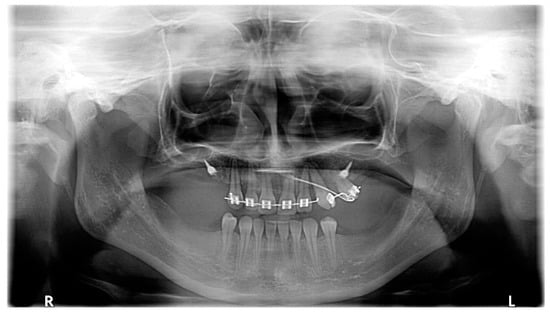

| March 2020 | The correct position of UL3; tooth no. 24 showed significant mobility; control panoramic X-ray: root resorption of tooth no. 24 (Figure 7); no possibility to conduct control visits on a regular basis due to COVID-19 pandemic—next appointment took place in November 2020. |

| May–August 2022 | Finishing; control panoramic X-ray (Figure 8); 1st canine relationships and midline consistency; debonding of the brackets; fixed upper and lower retainers’ placement (0.027″ × 0.011″ 8-strand braided SS), tooth no. 24 was not fixed to the retainer due to increased mobility. |